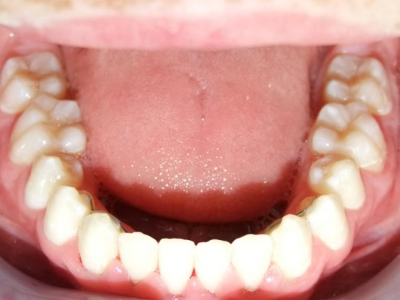

eindfoto

13-22 volledig vast onder- en bovenkaak + rotator

Retentie: wrap en c-c bar

Leeftijd bij retentie: 12 jaar